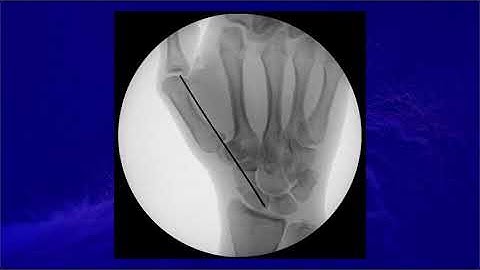

Technique of percutaneous fixation of scaphoid with headless compression screw @bipinhandsurgeon